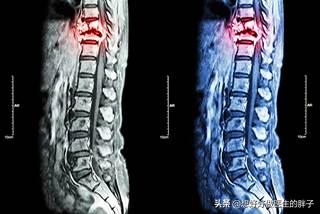

Magnetresonanztomographie von Knochenmetastasen

Nachweis von Knochenmetastasen in der Brustwirbelsäule